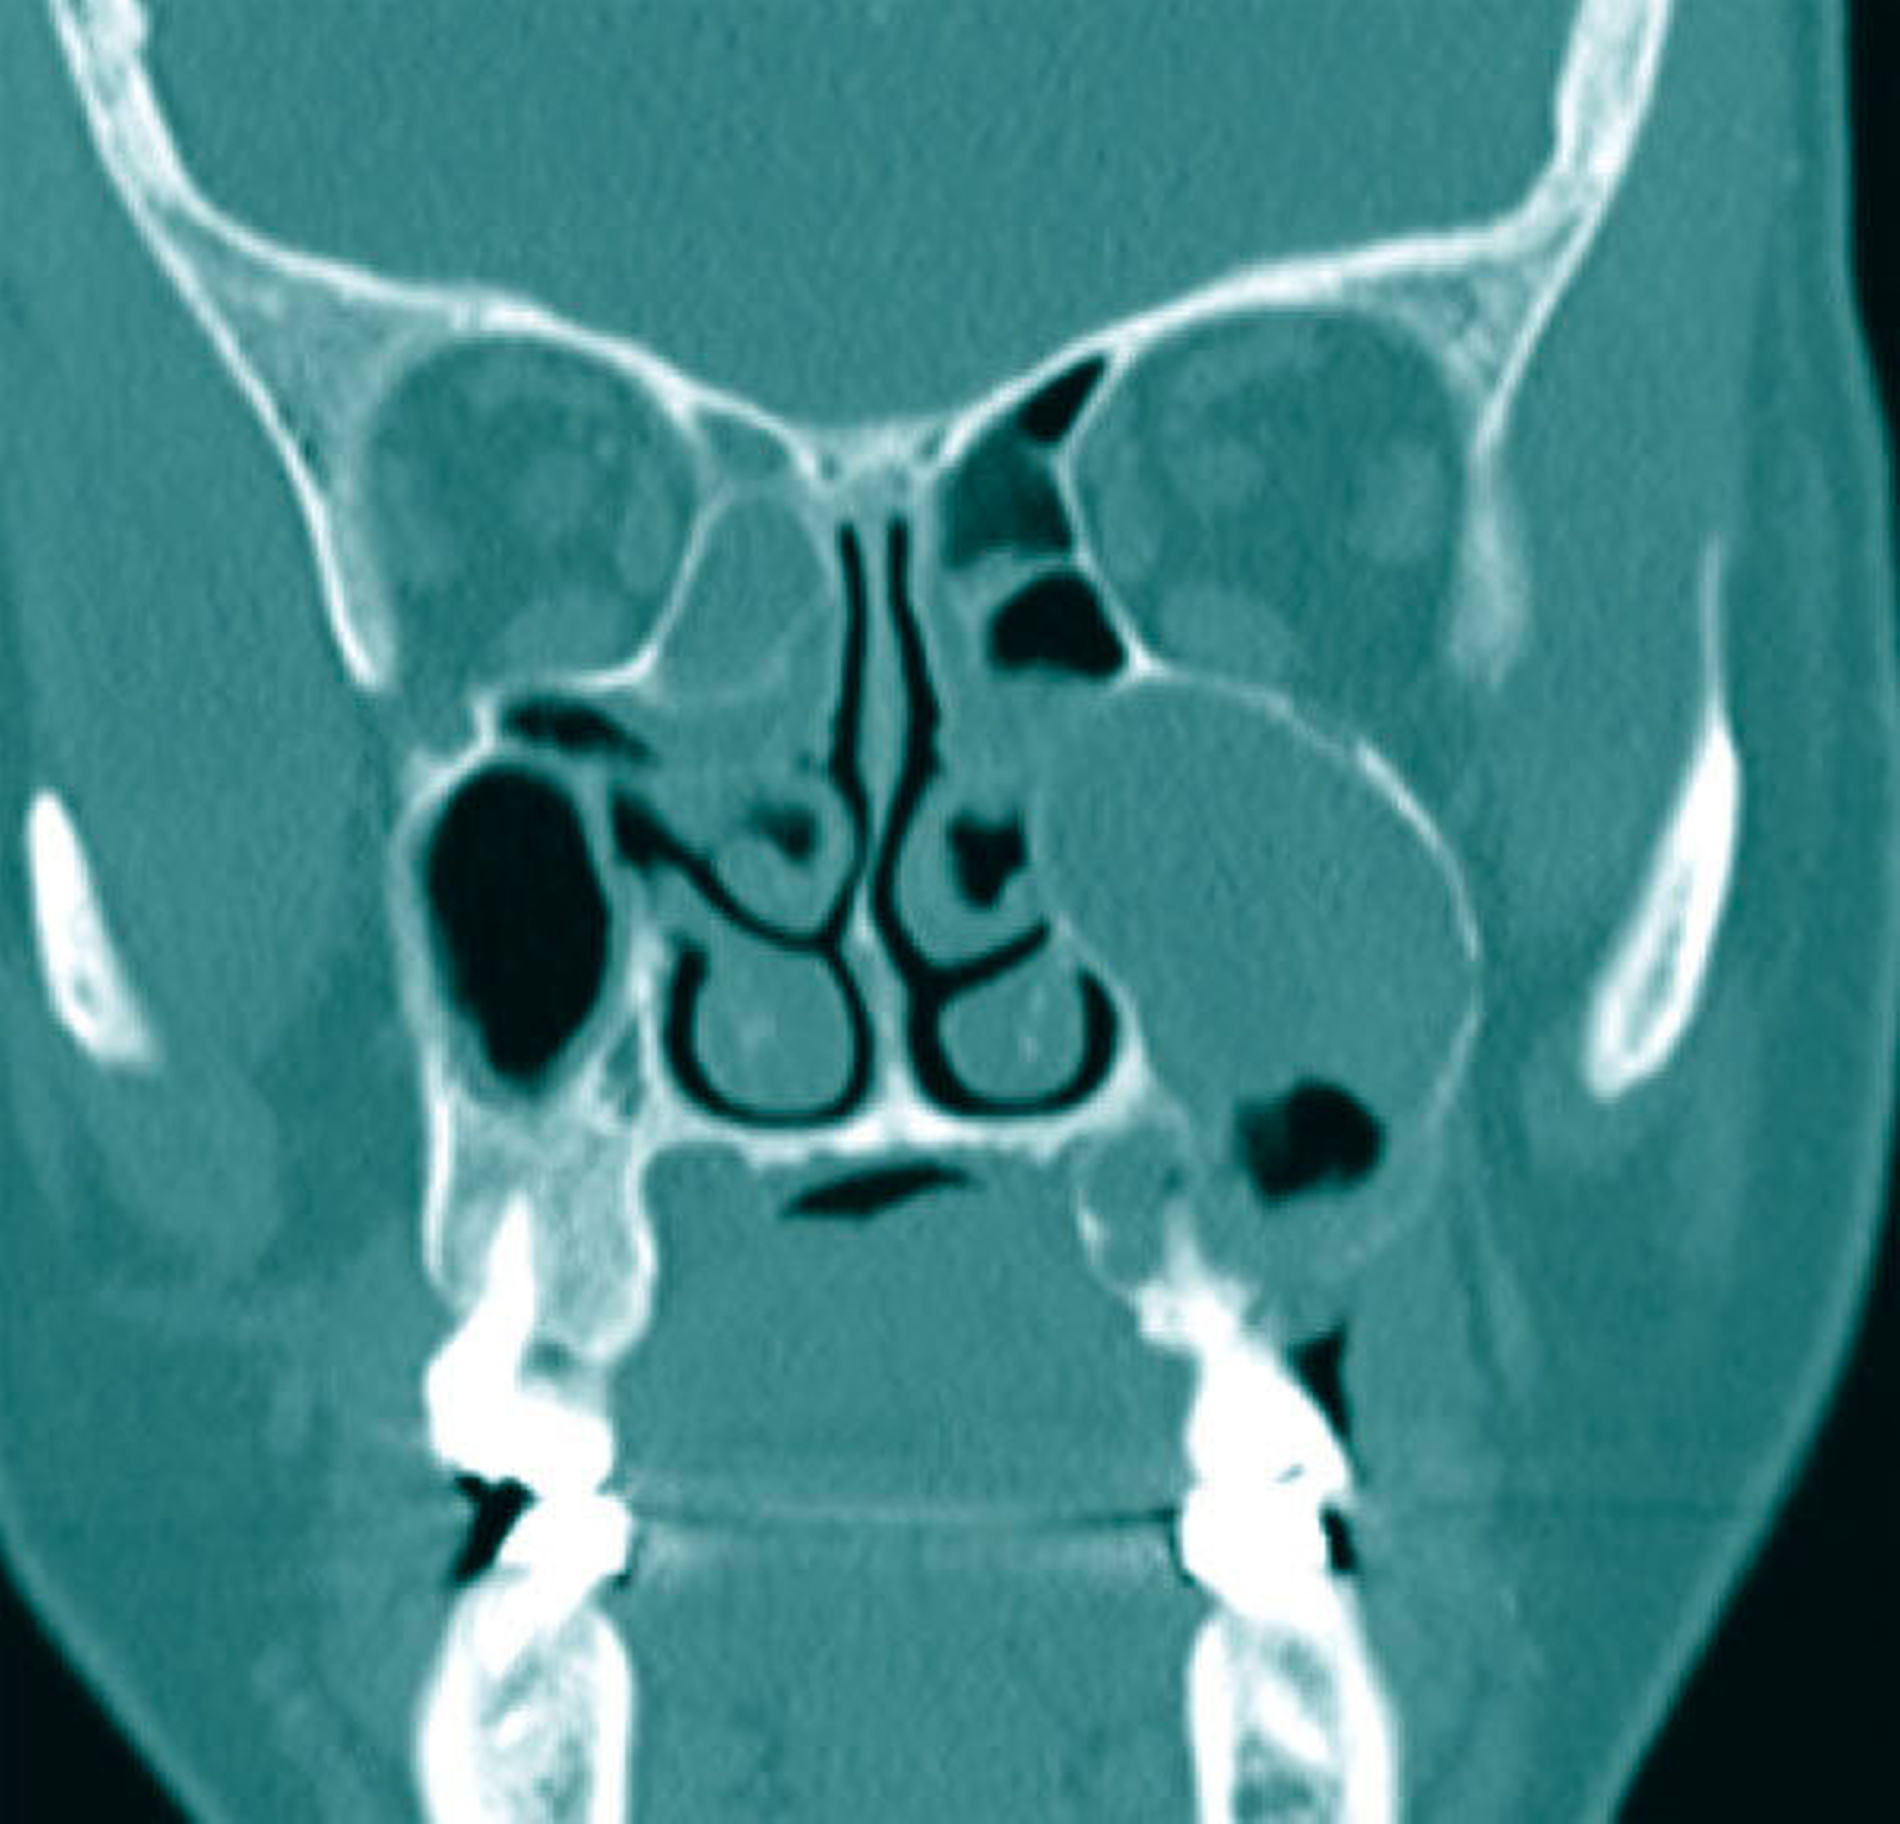

Die Allgemein- und Familienanamnese der Patientin war bis auf eine medikamentös eingestellte Hypothyreose unauffällig. Extraoral bestand kein auffälliger Befund, insbesondere keine Druckdolenz oder Nervdefizit über der Kieferhöhle links. In Regio 27 zeigte sich eine Mund-Antrum-Verbindung nach frustranem Deckungsversuch, aus der sich seröse Flüssigkeit entleerte (Abbildung 2). Der Zahn 26 reagierte negativ auf Perkussion und war avital. Nach sorgfältiger Aufklärung erfolgte die Resektion des Befunds in Intubationsnarkose. Folgend auf die Extraktion des Zahnes 26 (Abbildung 3) wurde eine Kastenresektion der linken Maxilla von distal des Zahnes 25 bis in den Tuberbereich bei makroskopischem Einhalten eines Sicherheitsabstands von 0,5 cm durchgeführt. Das narbig anmutende Gewebe in der Kieferhöhle wurde ausgeschält und en bloc mit dem Oberkieferresektat entfernt (Abbildung 4). Der Knochen wurde hier belassen, da er klinisch und radiologisch nicht infiltriert war.